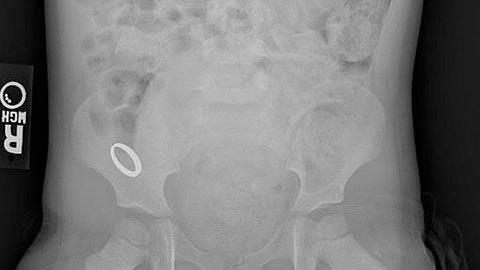

Η κόρη μου κατάπιε ένα παιδικό βραχιολάκι πριν είκοσι μέρες και ακόμα δεν το έχω βρει στα κόπρανά της. Είναι κάτι ανησυχητικό;